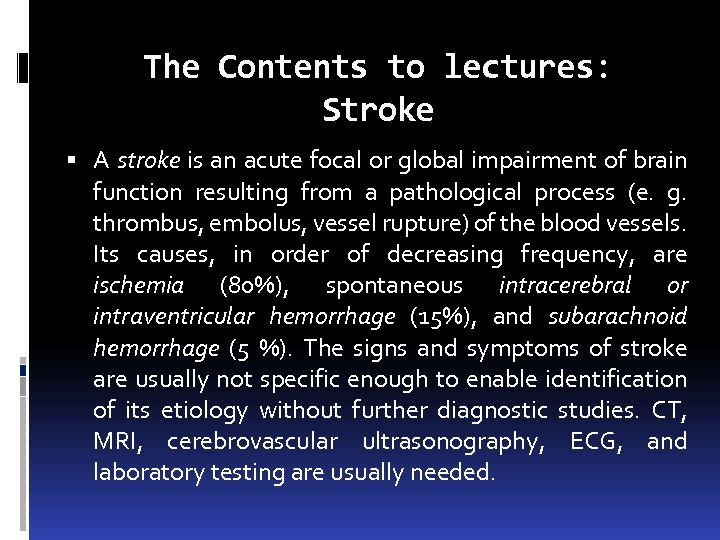

The Contents to lectures: Stroke A stroke is an acute focal or global impairment of brain function resulting from a pathological process (e. g. thrombus, embolus, vessel rupture) of the blood vessels. Its causes, in order of decreasing frequency, are ischemia (80%), spontaneous intracerebral or intraventricular hemorrhage (15%), and subarachnoid hemorrhage (5 %). The signs and symptoms of stroke are usually not specific enough to enable identification of its etiology without further diagnostic studies. CT, MRI, cerebrovascular ultrasonography, ECG, and laboratory testing are usually needed.

The Contents to lectures: Stroke A stroke is an acute focal or global impairment of brain function resulting from a pathological process (e. g. thrombus, embolus, vessel rupture) of the blood vessels. Its causes, in order of decreasing frequency, are ischemia (80%), spontaneous intracerebral or intraventricular hemorrhage (15%), and subarachnoid hemorrhage (5 %). The signs and symptoms of stroke are usually not specific enough to enable identification of its etiology without further diagnostic studies. CT, MRI, cerebrovascular ultrasonography, ECG, and laboratory testing are usually needed.